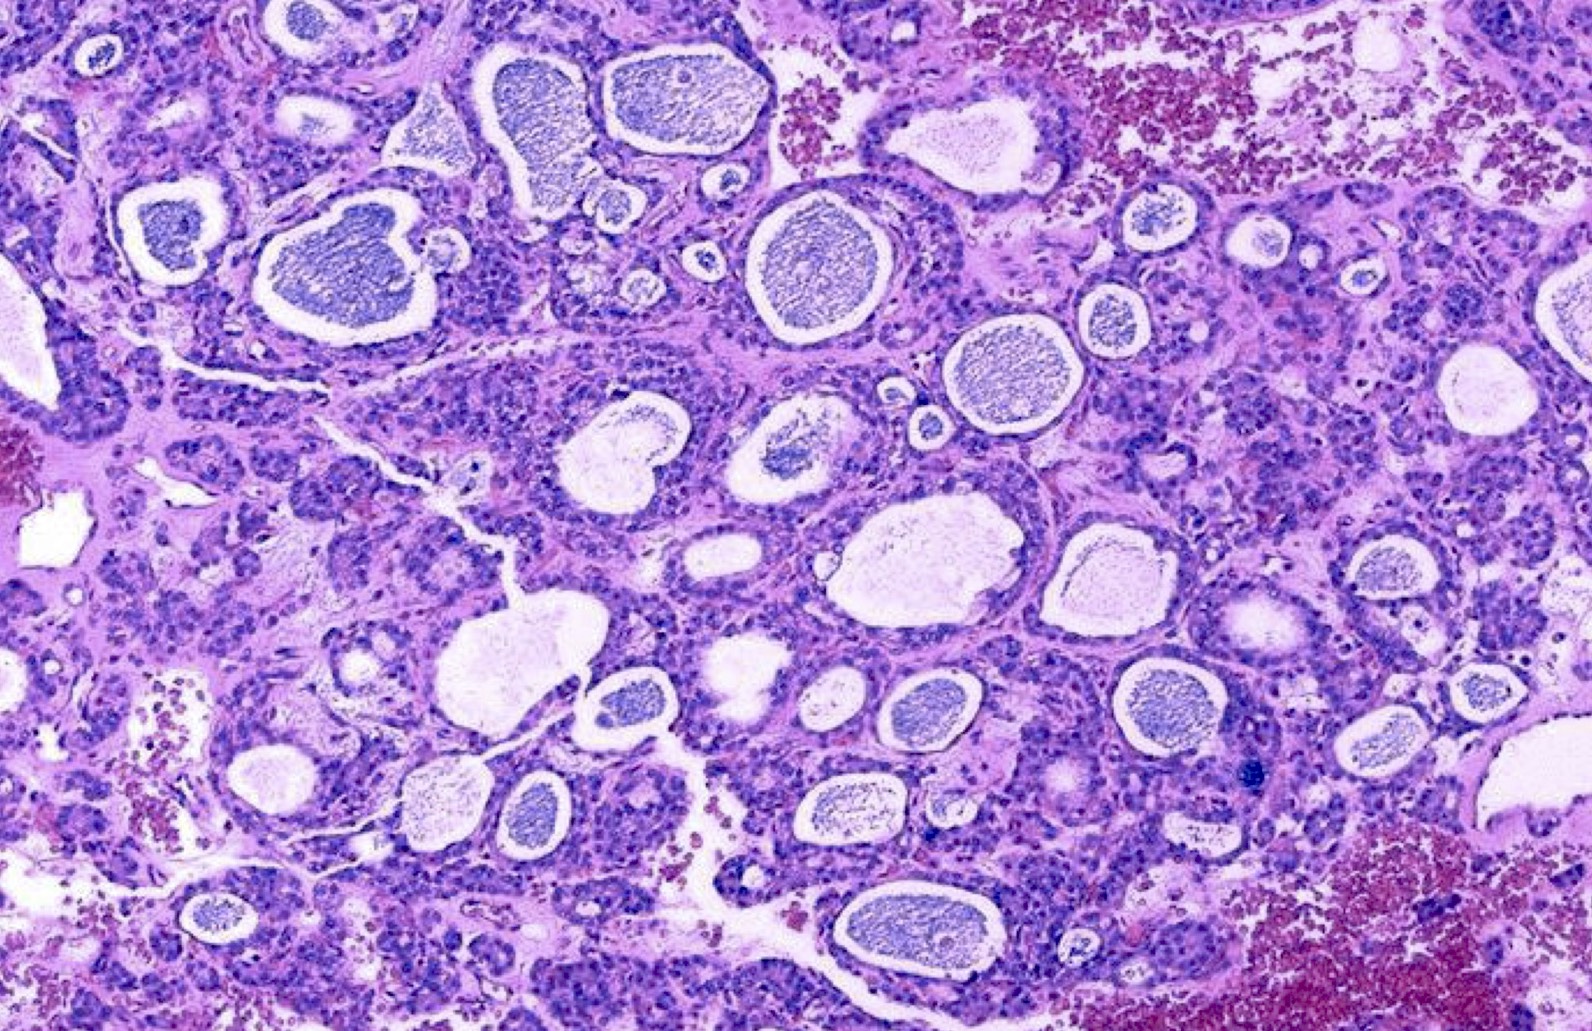

Microscopic (histologic) description

- Architecturally and cytologically different from surrounding gland

- Compression signs in surrounding thyroid tissue

- Encapsulated; thin or moderately thick capsule

- Architectural patterns (can be seen in any combination)

- Normofollicular (simple): size similar to normal thyroid follicles

- Microfollicular (fetal): smaller follicles, small amount of intraluminal colloid

- Macrofollicular (colloid): large follicles, flattened epithelium, abundant colloid

- Solid / trabecular (embryonal): minimal or no colloid

- Focal papillary pattern, occasionally; especially in hyperfunctioning adenoma and follicular adenoma with papillary hyperplasia

- Cuboidal to low columnar cells

- Small round nuclei, smooth nuclear boundary, uniformly hyperchromatic or euchromatic, dense chromatin, absent nuclear features of papillary thyroid carcinoma, nuclear score 0 or 1 (JAMA Oncol 2016;2:1023)

- Inconspicuous nucleoli

- Rarely, lipid filled vacuoles in cytoplasm

- Mitoses are uncommon

- Scant stroma

- Secondary changes: fibrosis, hyalinization, hemorrhage, hemosiderin deposition, edema, cystic degeneration, calcification, osseous or cartilaginous metaplasia

- Variants

- Hyperfunctioning adenoma (Plummer adenoma): tall columnar epithelium, papillary infoldings, vacuolated cytoplasm, watery colloid showing scalloping

- Follicular adenoma with papillary hyperplasia: cystically dilated follicles, intraluminal papillae

Microscopic (histologic) images

Contributed by Shipra Agarwal, M.D., Andrey Bychkov, M.D., Ph.D., Mark R. Wick, M.D., Asmaa Gaber Abdou, M.D. and AFIP

Patterns: